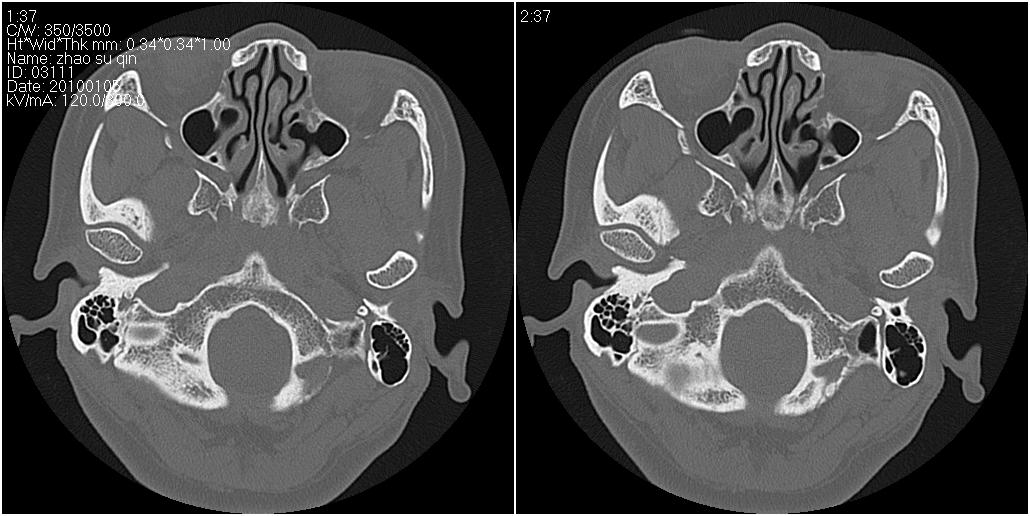

标题: CT24015:一个头部外伤患者进行鉴定,除了左侧筛板骨折,哪 [打印本页]

标题: CT24015:一个头部外伤患者进行鉴定,除了左侧筛板骨折,哪

看了几遍,其余未见明显骨折征。

左眶下裂部好像有骨折 似有小碎骨片

1)左侧筛板骨折。2)双侧筛窦炎症(或积血)。

其余未见明显骨折征。

请明示骨折部位。